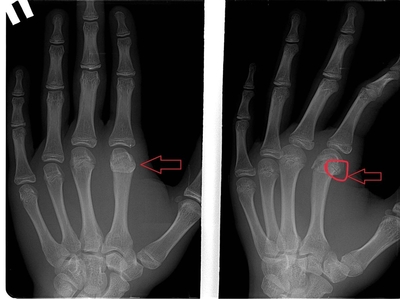

Ага, поняла, а почему на втором рентгене тоже видно перелом? Получается, все-таки не срослась кость или я не так вижу?

Второй снимок это процесс консолидации или сращения костной ткани. Линия перелома действительно прослеживается, но если обратите внимание, то заметите, что контуры уже более гладкие, сама линия менее четкая и в ней имеются более плотные участки. Это происходит формирование так называемой костной мозоли

Иллюстрация к комментарию